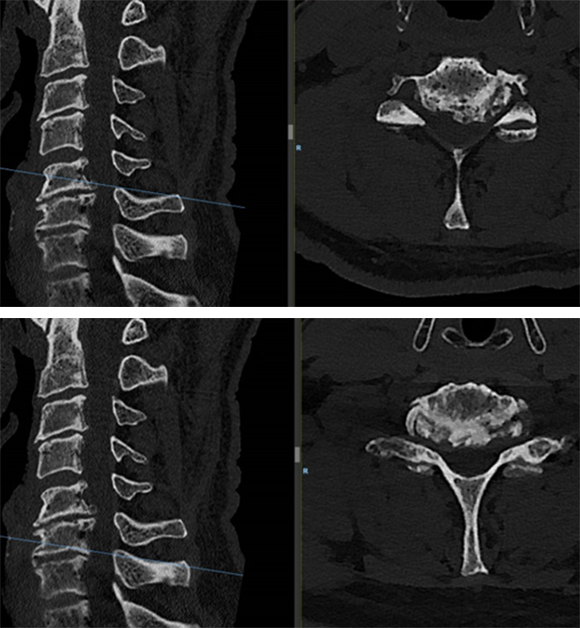

A computed tomographic scan showed large posterior osteophytes C5-6 and spondylosis anterior (Fig 6).